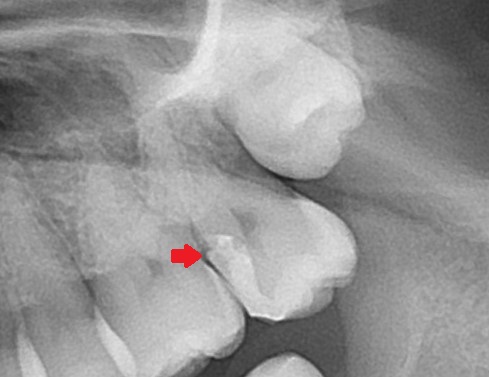

エックス線(レントゲン検査)で歯の中を見てみましょう。

一番奥に生えてきていない親知らずがあります。一つ手前の白く詰め物がされている歯です。

☝歯の神経は赤く記したここにあり、

神経に近く、ほぼ神経に触れるように詰め物がされています。

☝詰め物がうまく詰められておらず、飛び出て段差になっていることも見て取れます。